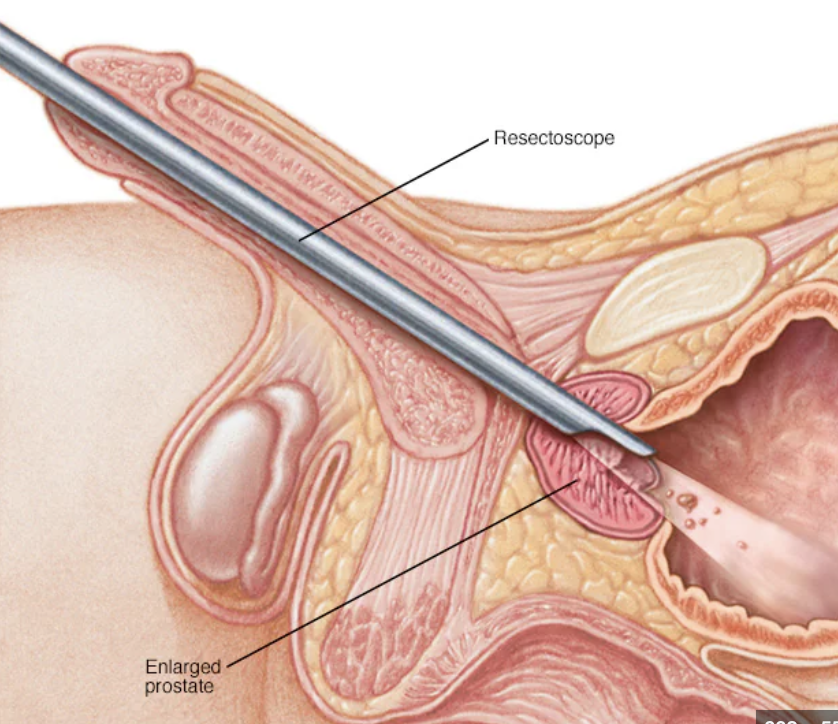

BPH

bein prostatic hyperplasia

pathologic condition

TURPS

transurethral resection of the prostate

surgical procedure